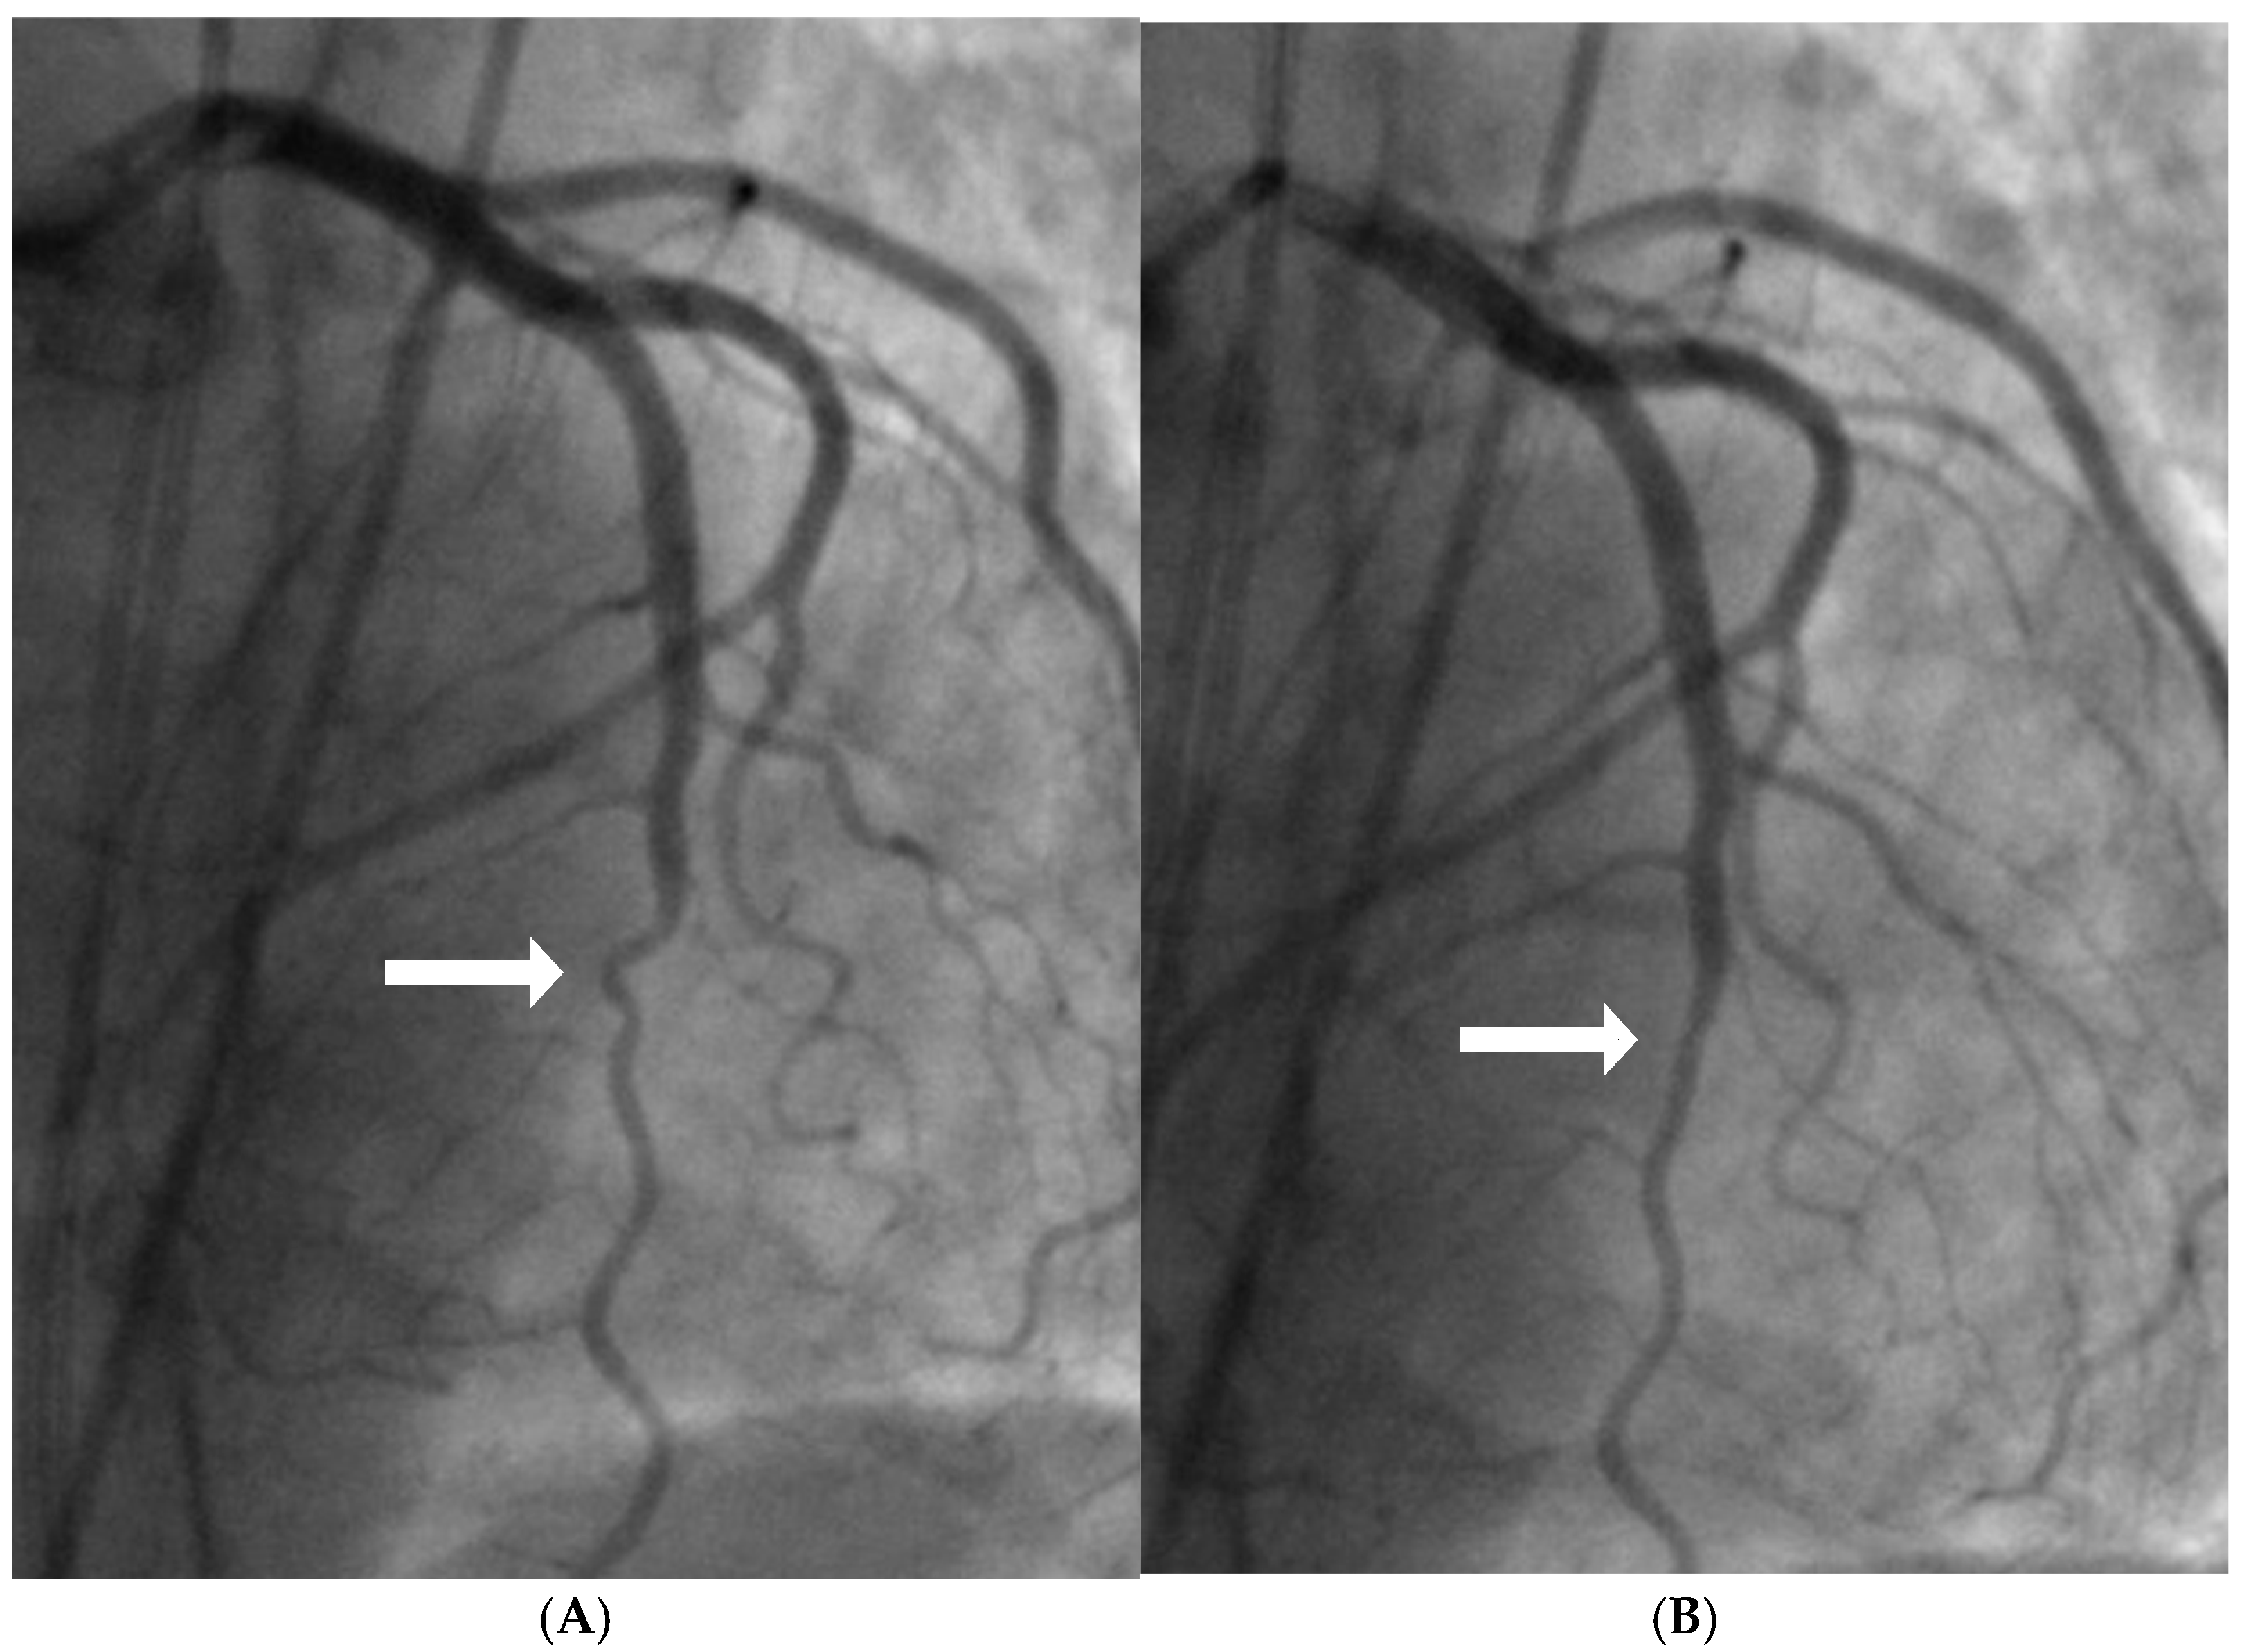

2.2. Mechanical Stress Due to Repetitive Bending at a Hinge Location

- Hinge Movement in Coronary Arteries:

- Coronary Angiographic Perspective: